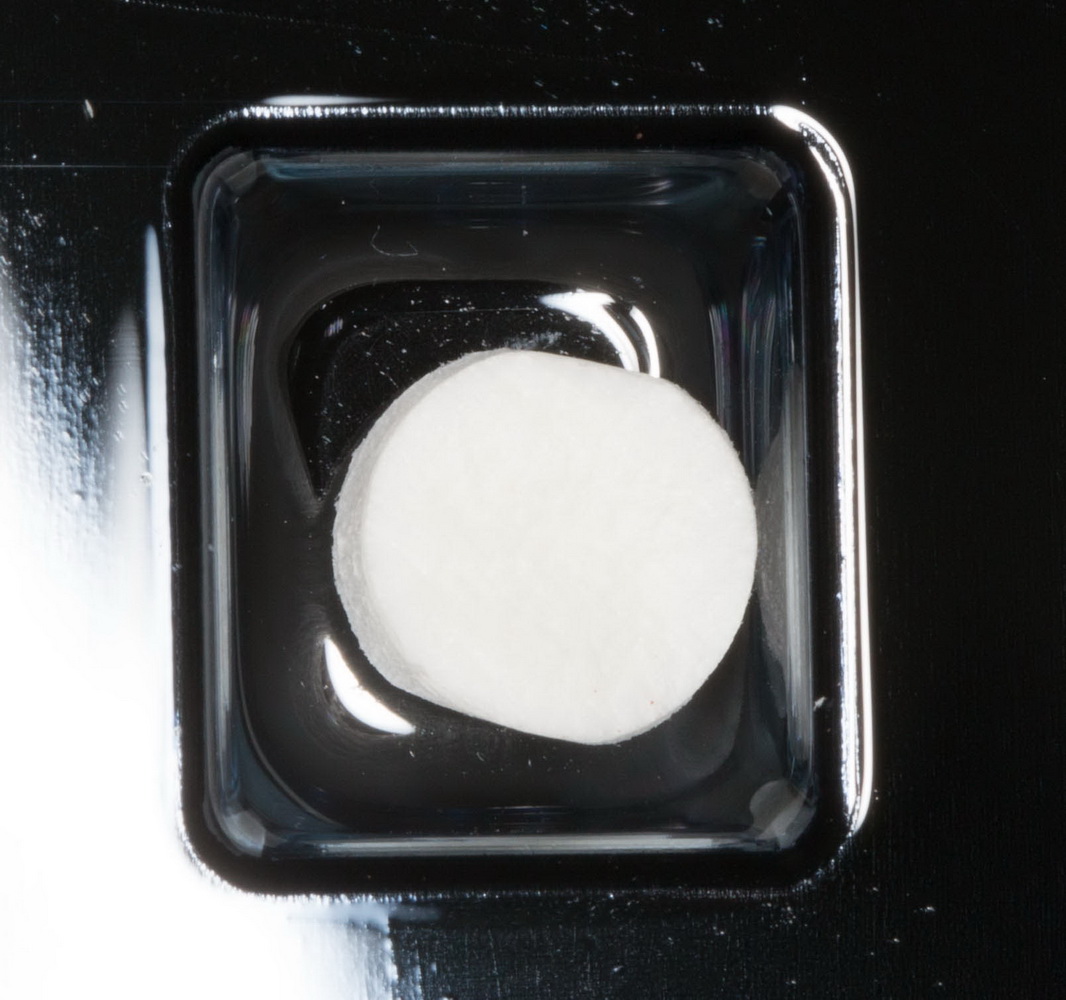

Биоматериал Geistlich Bioss. В таком небольшом объеме его можно (хотя и не рекомендуется) использовать без аутокостной стружки, «вчистую»:

Что делать-то? Есть еще один вариант. Это коллагеновая матрица. В данном случае Mucograft Seal. Почему Seal? Просто потому, что большой фрагмент матрицы нам не нужен, да и стоит он дорого (а наша пациентка — не самый богатый человек на планете). А Seal стоит недорого, при этом, это всё тот же Mucograft. Его размер (8 мм в диаметре) позволяет нам решить проблему с недостатком слизистой.

Прим. Компания Geistlich не одобряет подобную тактику, так как, с ее точки зрения,

Mucograft Seal имеет иное назначение.